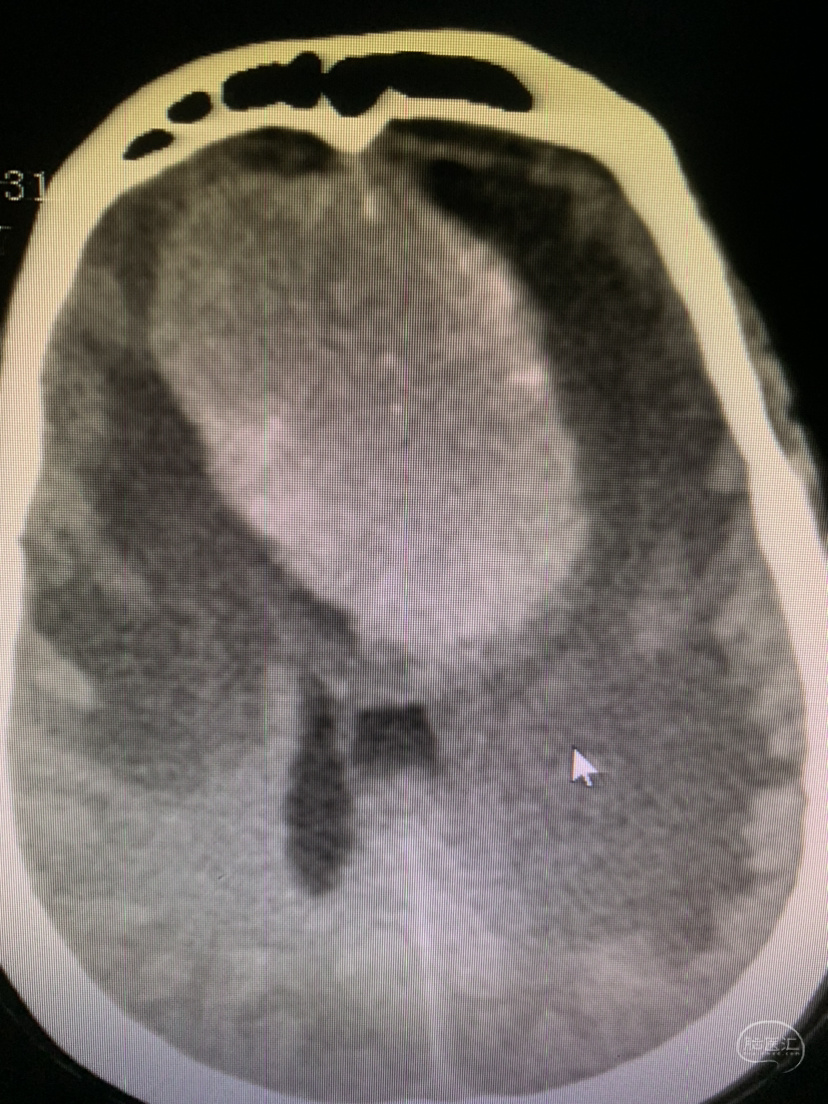

术前术后对比

术后CT